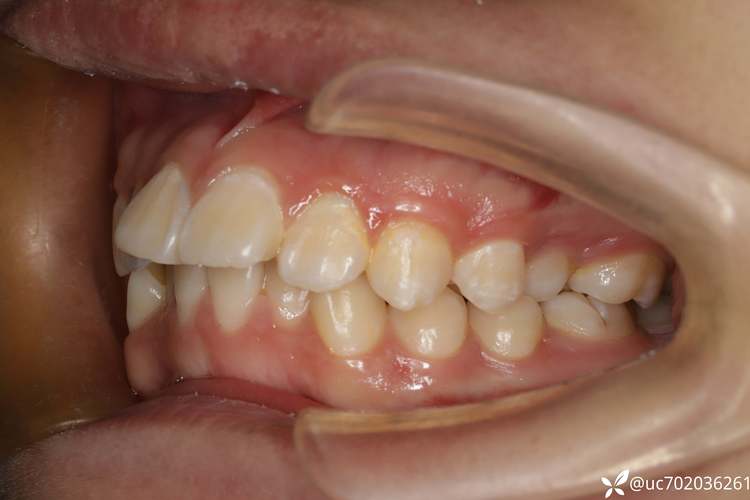

| 牙齿严重拥挤 | 上下牙弓存在明显间隙不足,牙齿排列不齐,甚至出现“扭转、重叠”,如“虎牙”被挤出牙弓外 | 拔牙可提供足够空间,让牙齿排列整齐,避免拥挤导致的清洁困难、龋齿、牙周病风险 |

| 前牙深覆盖(龅牙) | 上前牙突出过多,与下前牙的覆盖超过3mm,侧面观“嘴唇外翘” | 拔除部分前磨牙,可内收上前牙,改善龅牙问题,调整唇齿关系,让面部轮廓更协调 |

| 前牙深覆合 | 上前牙盖过下前牙过多,甚至下前牙咬到上颚软组织,可能伴随下面部短缩 | 拔牙后通过压低上前牙、升高下后牙,打开咬合空间,避免咬合创伤和面部发育异常 |

| 上下牙弓宽度不协调 | 上牙弓过窄或下牙弓过宽,导致“反合(地包天)”或“锁合” | 拔牙可调整牙弓宽度,让上下牙齿咬合更顺畅,改善咀嚼功能 |